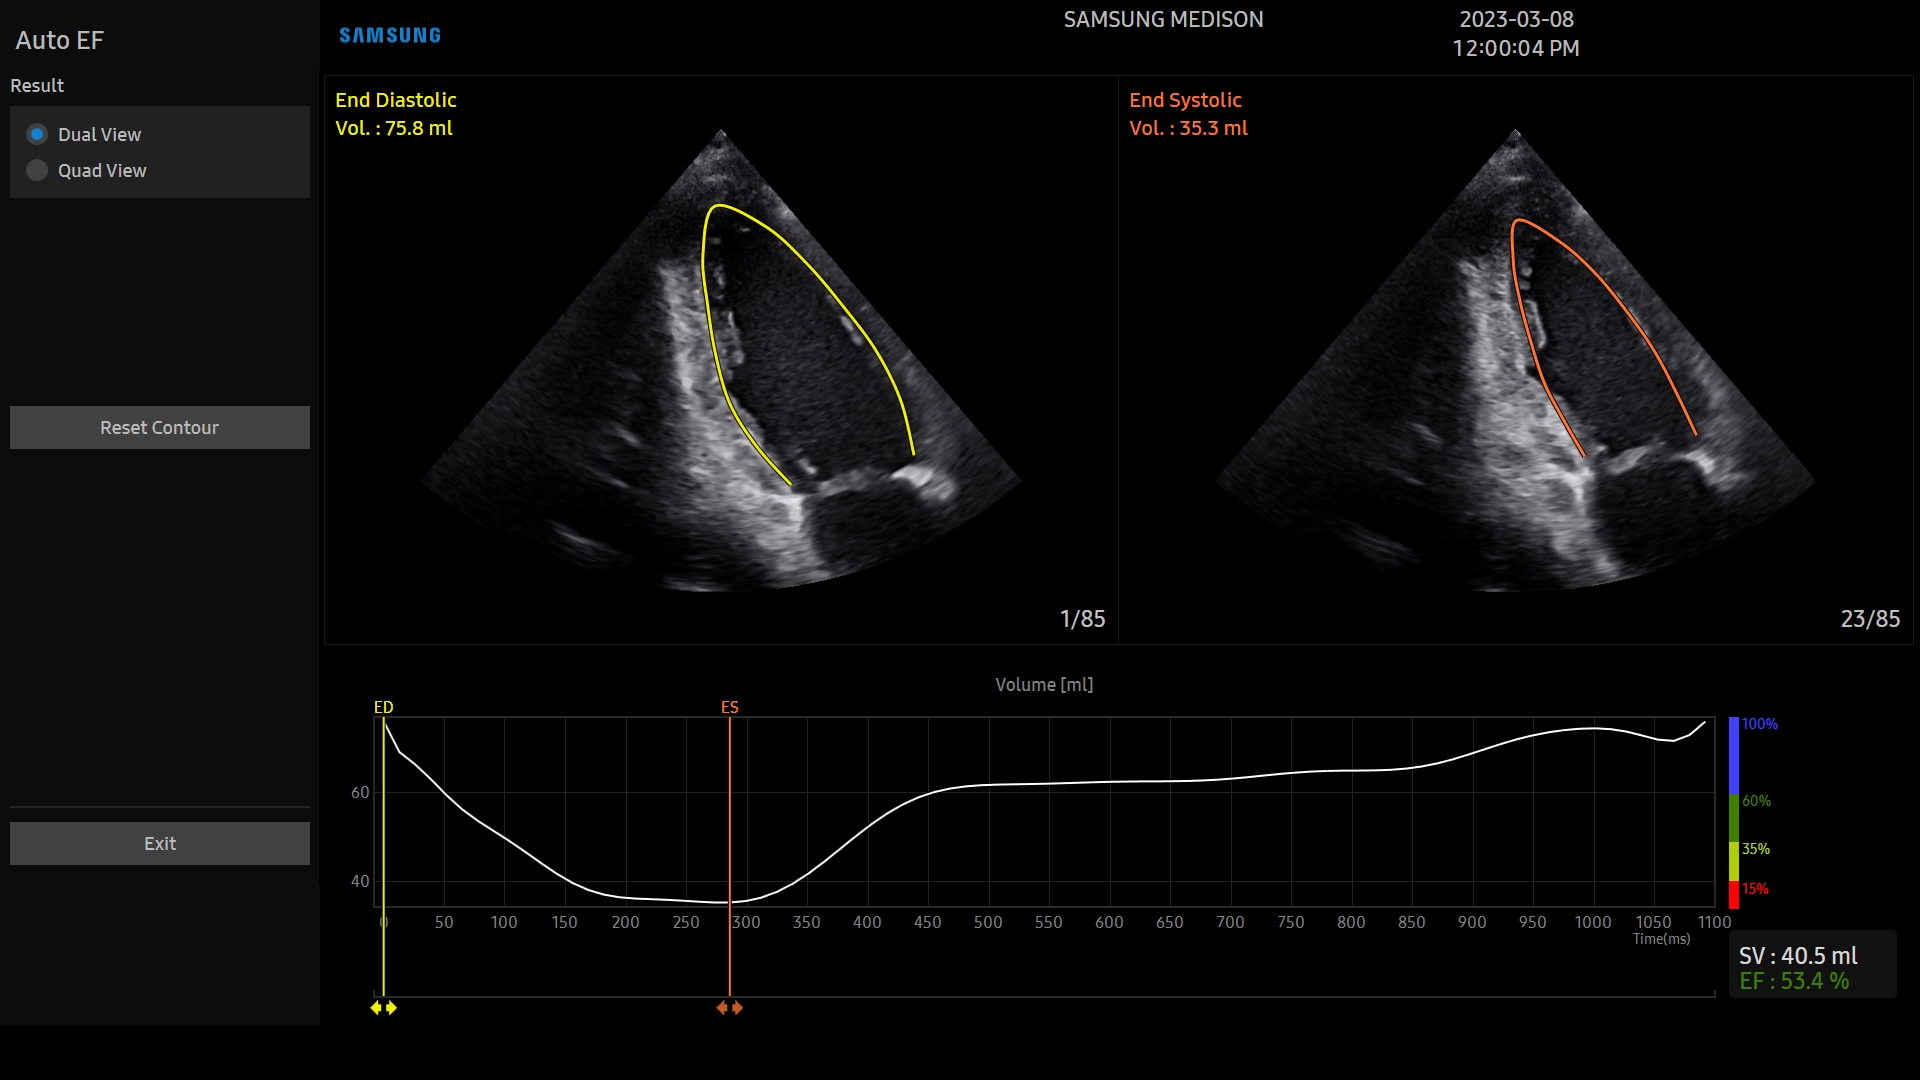

El V8 incluye herramientas avanzadas de diagnóstico asistido como HeartAssist™, Strain+™, StressEcho™, AutoEF™, ArterialAnalysis™ y AutoIMT+™, que automatizan y agilizan el análisis cardíaco ofreciendo mediciones fiables y reproducibles, vitales en cardiología